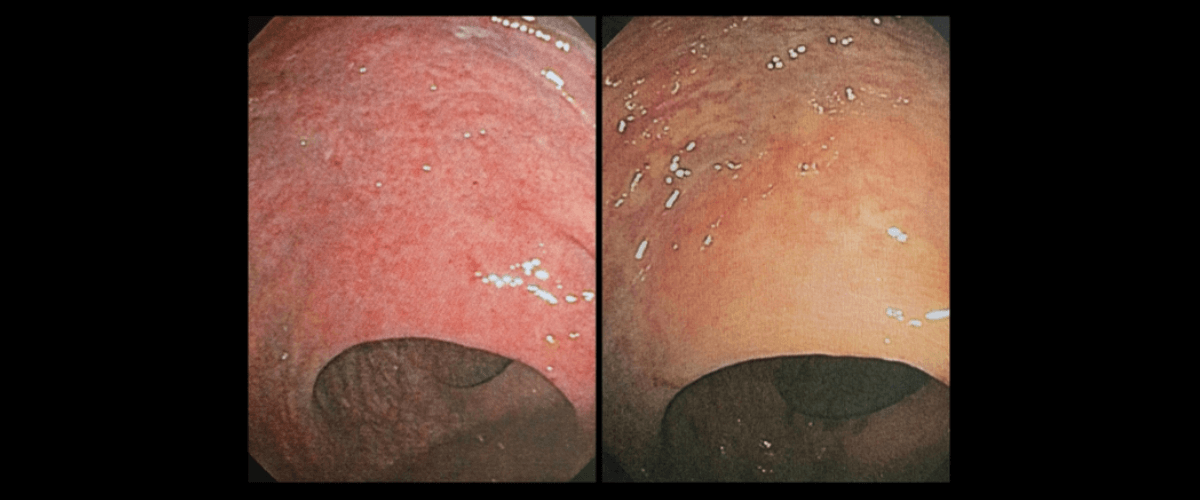

July 30, 2020 Ulcerative Colitis

My Ulcerative Colitis Is in Remission

As at July 15, 2020, my ulcerative colitis was in clinical, endoscopic, and histologic remission.